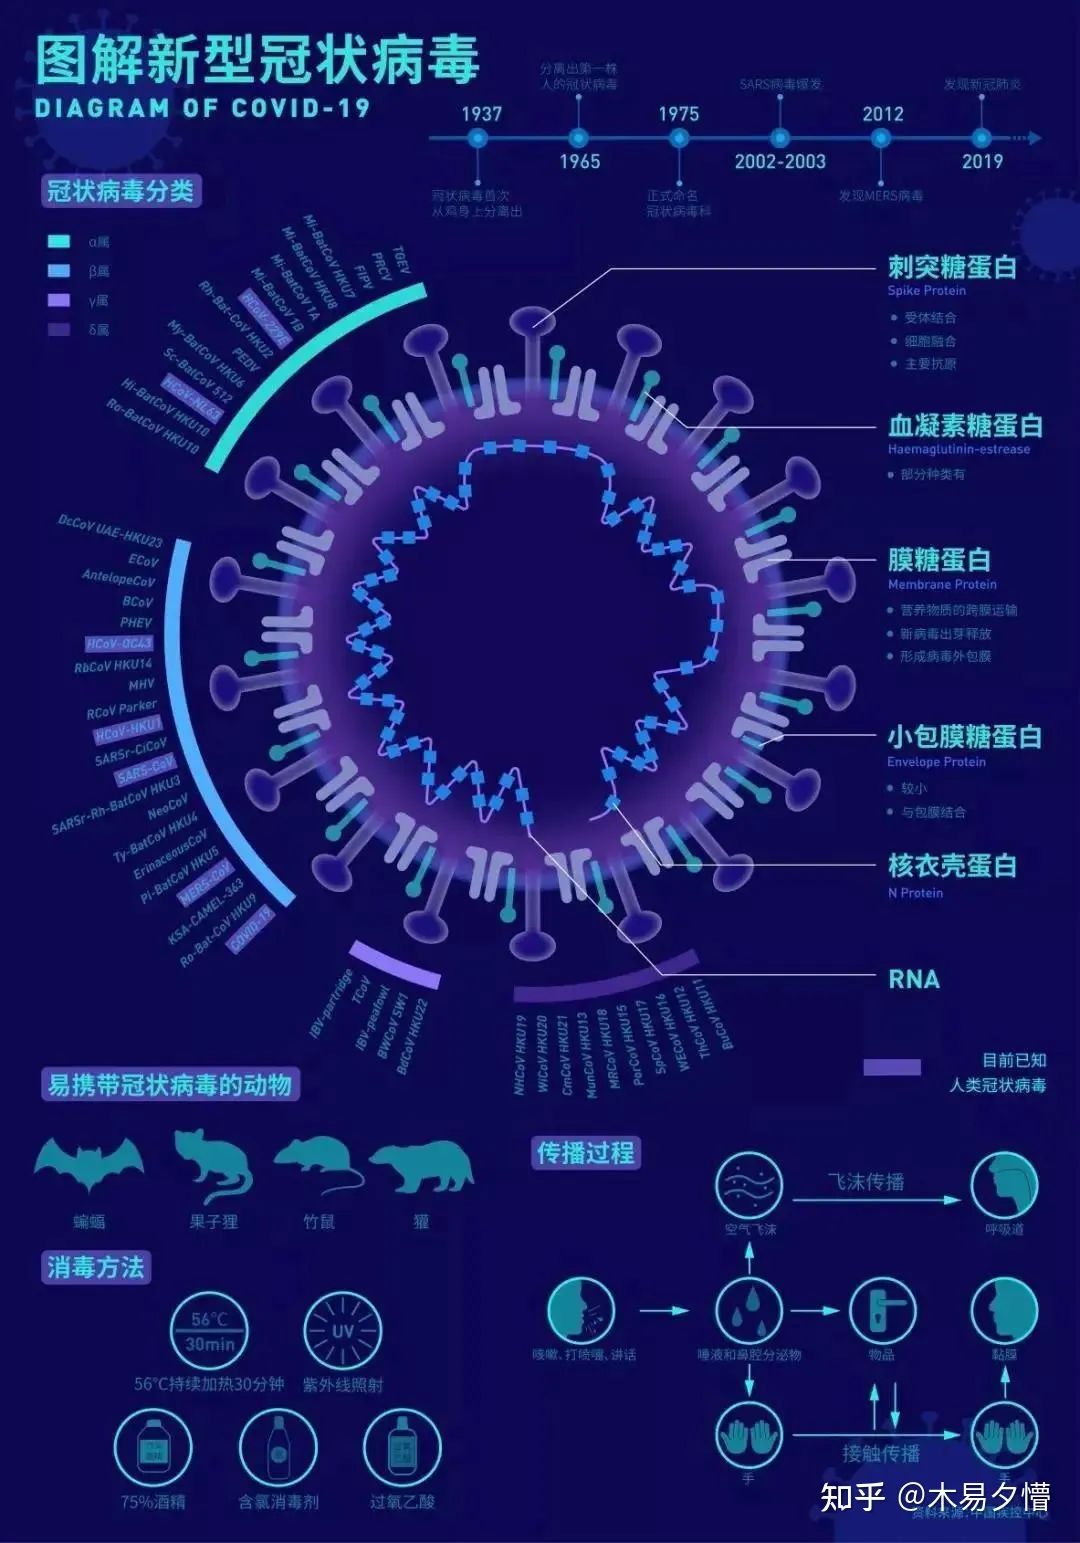

《图解新型冠状病毒》

作者:潘叶娣 | 南京艺术学院设计学院

设计说明:通过对新型冠状病毒的结构、分类、传播过程等方面的分析进行了可视化设计,以图解的方式清晰易懂地呈现出来,让大家更直观地了解新型冠状病毒。